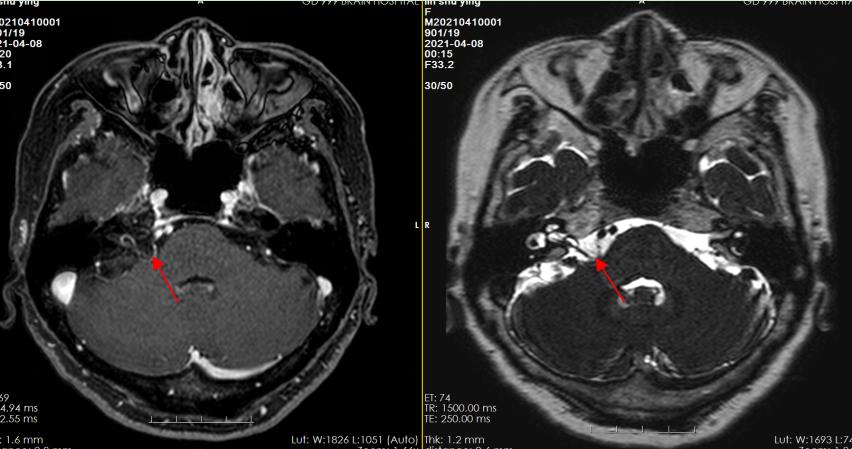

头颅MRI三叉神经薄层扫描显示:右侧面神经根部前下缘一小血管骑跨走行,局部颅神经及脑干受压。

与此同时,患者的肌电诱发电位提示:瞬目反射异常;右侧可见MD-OC反应;EMG可见肌束震颤波。